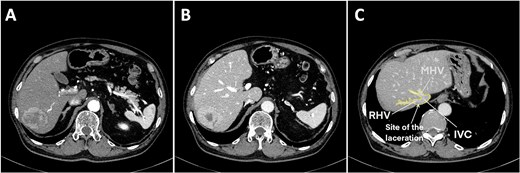

A 75-year-old man was referred to our institution for evaluation after the incidental finding of a liver tumor during routine surveillance. The medical history included a cerebral infarction 11 years ago, type 2 diabetes, hypertension, and percutaneous coronary intervention. He was taking aspirin daily, which was discontinued several days before surgery. The patient was asymptomatic at the time of presentation. The laboratory findings were normal and liver function was preserved (Child–Pugh A5). Dynamic contrast-enhanced computed tomography (CT) showed a solitary 53-mm lesion in segments 6 and 7, which was consistent with hepatocellular carcinoma (Fig. 1A and B). A laparoscopic posterior sectionectomy was planned.

Preoperative contrast abdominal computed tomography of a hepatocellular carcinoma tumor on the posterior segment. (A) Arterial phase, (B) venous phase, and (C) right and middle hepatic vein image with the laceration site marked. Abbreviations: IVC, inferior vena cava; RHV, right hepatic vein; MHV, middle hepatic vein.